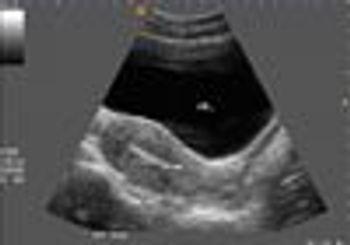

Mother is sure of LMP 17th Nov/98 ( EDD = 24/8/99). On ultrasound scan (17/7/99) the average gestational age is only 31 weeks, ie the ultrasound derived EDD=18/9/99.